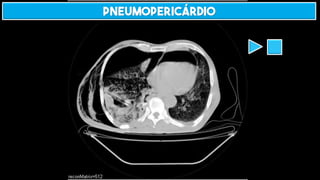

PNEUMOPERICÁRDIO

Sinal do diafragma contínuo